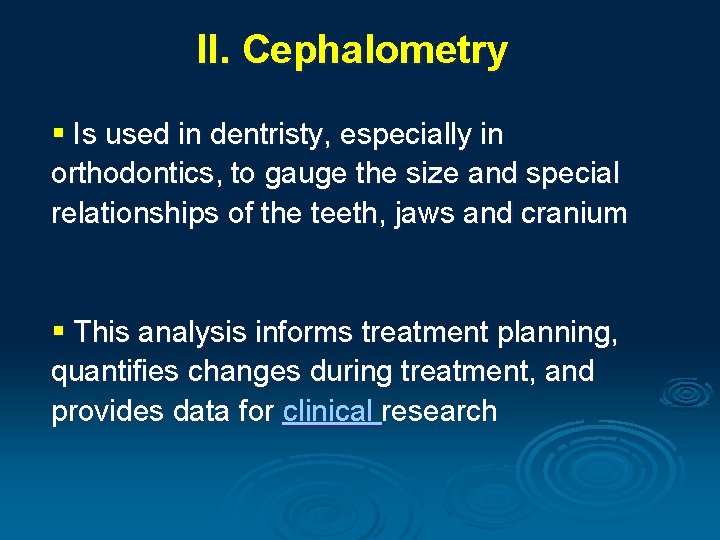

II. Cephalometry § Is used in dentristy, especially in orthodontics, to gauge the size and special relationships of the teeth, jaws and cranium § This analysis informs treatment planning, quantifies changes during treatment, and provides data for clinical research